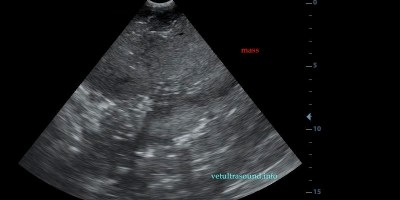

Κατηγορία: Abdominal Ultrasound